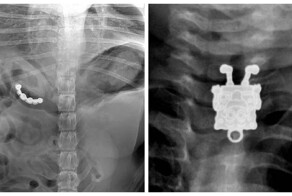

Рентгеновские снимки, которые показывают нам, что глотают люди по неизвестным причинам.

Понятное дело наркотики, ну а вилки и пружины от кровати, зачем?

Магниты